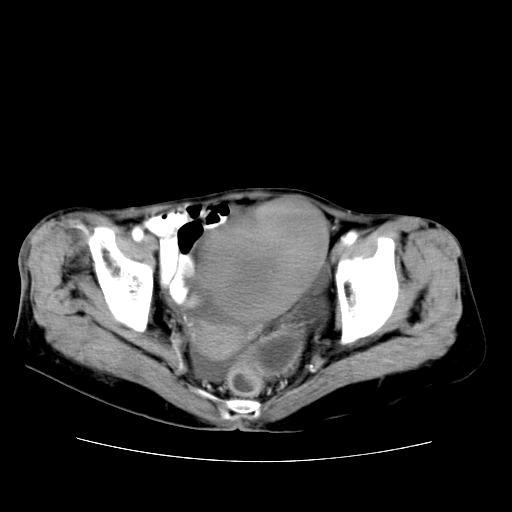

女性,72岁。

主诉下腹部坠痛不适1年余。

子宫增大如孕3月大小,质软,活动可,无压痛。

b超提示:盆腔(子宫前方)低回声团块。

临床诊断:盆腔肿块查。

1、这个肿瘤密度均匀,增强后轻中度均匀性强化,与左侧附件关系密切,肿瘤边缘光整、清晰。

2、左侧卵巢增大呈8×8×10cm大小,实性,表面光滑,边清,左侧输卵管爬行于左卵巢上,子宫萎缩。右输卵管、卵巢萎缩。

3、病理号:092658

左侧卵巢纤维瘤(性索间质肿瘤)

卵巢纤维瘤为良性卵巢性索间质肿瘤,常为单侧发病,当合并腹水或胸腹水时称麦格斯(meigs)综合征,肿瘤切除后胸腹水可消失。ct表现为盆腔内边界清楚的圆形或椭圆形肿块,常有分叶或不规则;肿瘤多为实性,少数为囊性、囊实性,完全囊性者可见壁结节。实性部分与子宫等密度;增强扫描常为轻度强化或几乎不强化。